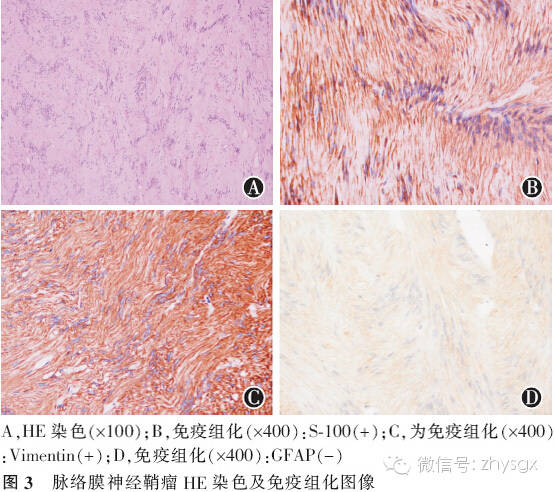

患者,女,37岁,因“右眼视物不清伴眼前黑影遮挡6年,胀痛2年”于2009年12月入院。既往:双眼高度近视,10年前行双眼LASIK手术。眼科检查,视力:右眼无光感,眼压51.7 mmHg;左眼0.8,眼压11.3 mmHg。右眼结膜混合性充血,角膜雾状混浊,前房中深,瞳孔4 mm,对光反射迟钝,晶状体前囊下见棉絮状混浊,眼底窥视不清;左眼检查大致正常。辅助检查:眼部B超示:右眼玻璃体腔内可探及球形实性病变,边界清晰,病变内回声不均匀,并可探及带状回声与其相连,考虑为右眼球内占位,继发性视网膜脱离(见图1);右眼眼轴长27.0 mm,左眼眼轴长26.9 mm。MRI检查示右眼球内后极部可见大小约1.5 cm×1.4 cm的信号灶,病灶信号均匀,边界清晰;相对玻璃体其在T1WI上呈稍高信号,T2WI上呈低信号;相对脑组织其在T1WI上呈等信号,T2WI上呈稍高信号;病灶局部的眼球壁向后突出、隆起;可见视网膜脱离。左眼球及脑部未见明显异常(见图2)。入院诊断:右眼球内肿物,右眼继发性视网膜脱离,右眼继发性青光眼。入院后予降眼压等对症处理,并于2009年12月22日局麻下行“右眼球摘除术”,术中见眼球壁完整,切开后呈鱼肉状。术后病理报告示:脉络膜神经鞘瘤。病理切片HE染色:显微镜观察可见肿瘤细胞为梭形,细胞核细长,深染,呈不典型栅栏状排列,部分呈束状排列。免疫组织化学染色:肿瘤细胞分别对S-100染色呈阳性,波形蛋白(Vimentin)染色呈阳性,胶质纤维酸性蛋白(glial fibrillary acidic protein,GFAP)、增殖细胞核抗原(Ki-67)、平滑肌肌动蛋白(smooth muscle actin,SMA)染色均呈阴性(见图3)。